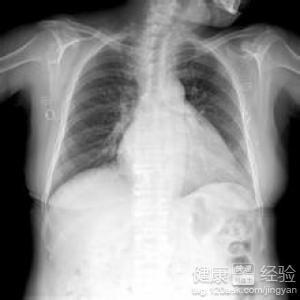

1風濕性的心髒病是心髒類疾病中的一種,根據多年的數據統計可以發現,女性患者要多於男性,而且風濕性心髒病在早期並沒有特殊的症狀可以觀察,隨著時間的推移才慢慢顯示出心力衰竭等。